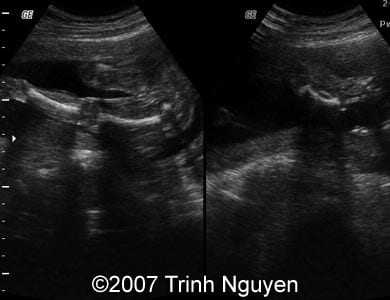

Images 1, 2: The image 1 shows a normal appearance of the left fetal leg (left part of the image 1), and a shortened bowed bone of the right lower leg (right part of the image 1). The image 2 shows deformed bones of the right right lower leg.

1

2